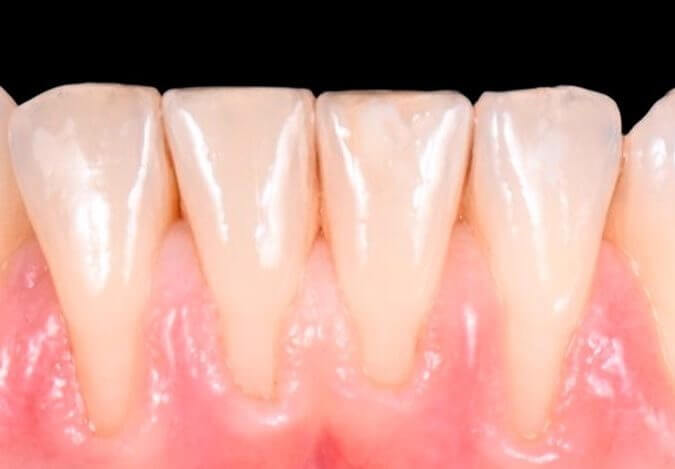

La ortodoncia corrige dientes mal posicionados y mejora la oclusión, favoreciendo tanto la estética como la salud bucal.

En IdenClinic tratamos a niños y adultos con distintos sistemas: brackets metálicos, estéticos y ortodoncia invisible.

Esta última utiliza férulas transparentes que pasan inadvertidas y alinean los dientes de forma progresiva y cómoda.

Analizamos cada caso con precisión digital y planificaciones personalizadas, logrando una sonrisa armónica, una mordida funcional y resultados estables sin comprometer la imagen del paciente durante el tratamiento.